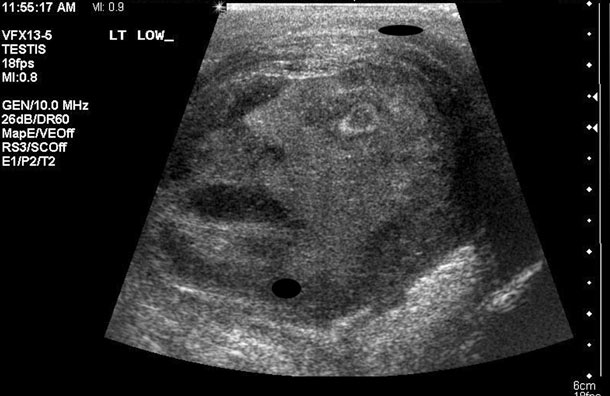

When a 45-year-old dude from Ontario, Canada went to have an ultrasound of his testicle after feeling some pain, the last thing he expected was to see what appears to be a screaming face. But yeah, either that’s a picture of his future son or there’s somebody literally living in his nut. I guess the doctor’s prognosis must’ve involved an exorcist. Can you imagine a priest splashing holy water on this poor guy’s nutsack while screaming, “The power of Christ compels you?” Or maybe it’s like blue balls, except face balls. At least Queen James won’t have this problem because he doesn’t have any. I know, I know. Low blow.